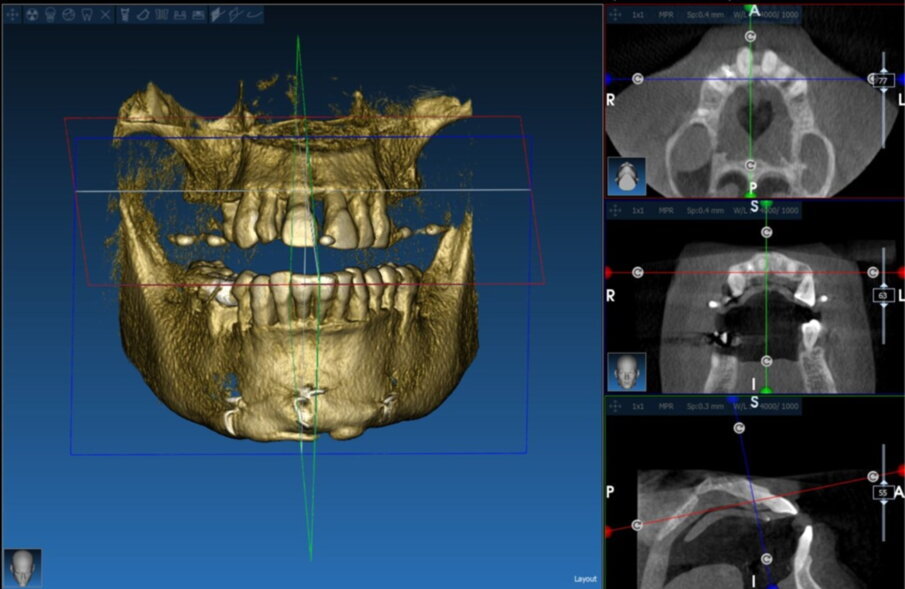

Matching del file STL con il file DICOM (Figg. 15, 16)

Il software consente di visualizzare sezioni assiali, coronali, sagittali, trasversali nonché ricostruzioni panorex e 3D (rendering), e di ottenere la sovrapposizione dei dati DICOM con i file STL, ottenuti mediante scansioni ottiche, intra o extraorali. Questi software permettono di selezionare i siti più adatti, la forma e la lunghezza di ciascun impianto, e permettono di prevedere la necessità e la quantità di un eventuale innesto osseo

(Figg. 17-18).

Figg. 15, 16_ Pianificazione con software Realguide.